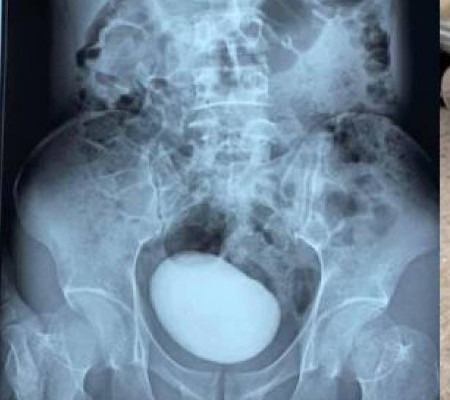

Uma foto de uma pedra gigante que foi retirada da bexiga de uma mulher está causando furor nas redes sociais. Segundo o Clarín, tudo começou quando a vietnamita de 34 anos foi à emergência de um hospital em Thay Nguyen, no Vietnã, se queixando de fortes dores abdominais. Informações do Metro.

Após perceberem que seu abdômen estava mais duro que o normal, os médicos decidiram fazer uma tomografia computadorizada para obter uma imagem do que estava lá dentro. O que eles não esperavam, entretanto, era encontrar uma enorme massa redonda alojada em seu abdômen.

Ela teve que ser submetida a uma cirurgia de emergência para remover a pedra de mais de dez centímetros de comprimento e 400 gramas. Nas redes, onde o caso viralizou, muitos usuários comentaram que não acreditam em como a mulher conseguiu levar uma vida relativamente normal e por tanto tempo com uma pedra dessas alojada em sua bexiga.

De acordo com um estudo publicado em 2014 por uma revista especializada em urologia, cálculos com mais de 100 gramas são muito raros, com menos de 85 casos registrados e documentados ao longo dos anos. Além disso, a pedra da mulher é a mais longa já extraída.